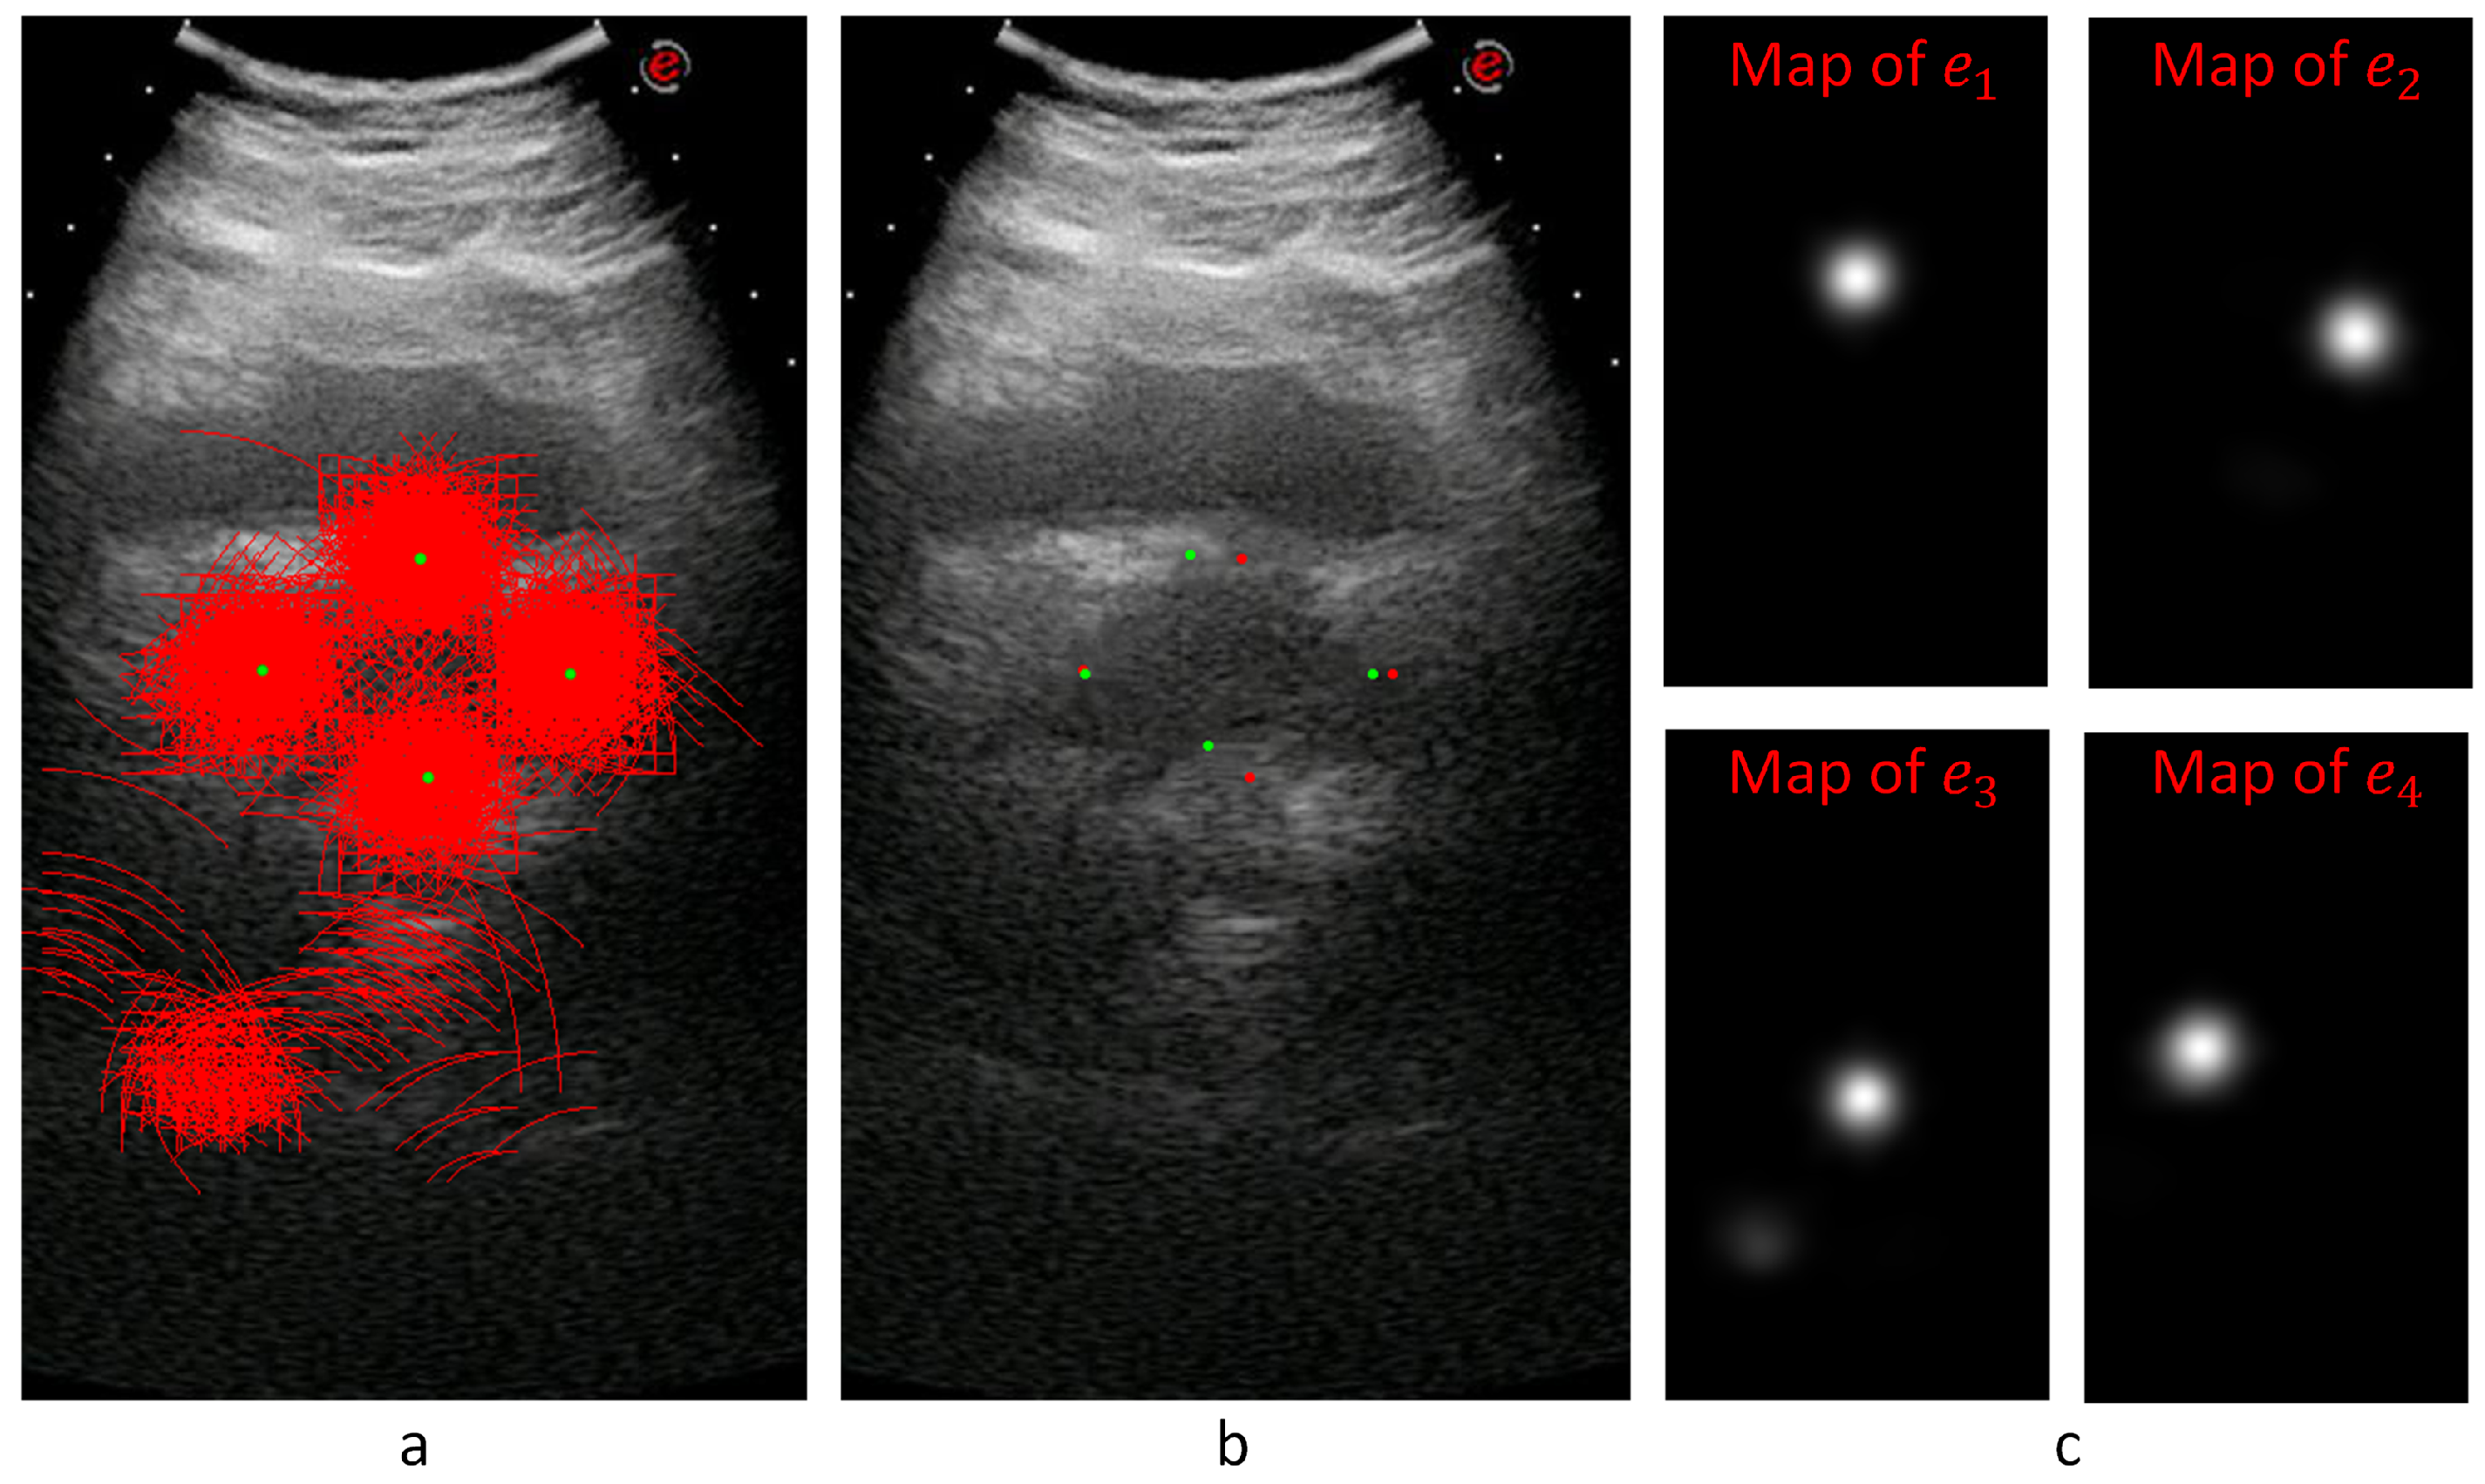

Figure 8 shows an example for the voting maps, arcs, and detected diameter endpoints. In Figure 8a, the arcs are drawn in red with the detected diameter endpoints in green. This sample image does not show the thickness to represent the locations of the arcs better. Figure 8b shows the detected points with red dots, while the manually annotated points are shown with green dots. Figure 8c shows the voting maps of each diameter endpoint. A Gaussian smoothing filter convolves these maps to suppress the noise in these images.

Figure 8. For a given transverse image, (a) shows the voting arcs (without thickness); (b) shows the detected points (reds are expert marked locations, while greens are the detected locations of the diameter end points); and (c) shows the voting maps for e 1 , e 2 , e 3 , and e 4 endpoints.